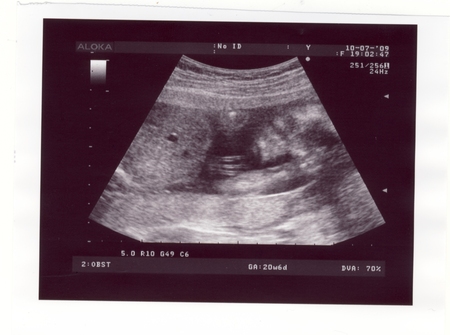

Здесь нам 20 неделек и 6 дней)))

Ну это их работа...они это изучали и им то уж понятнее где там что и как рассмотреть и измерить)) На картинке видно что голова справо, там видно и глазки и ротик. И под голову ручку положил, рядом вторая ручка виднеется, только её уже плохо видно...